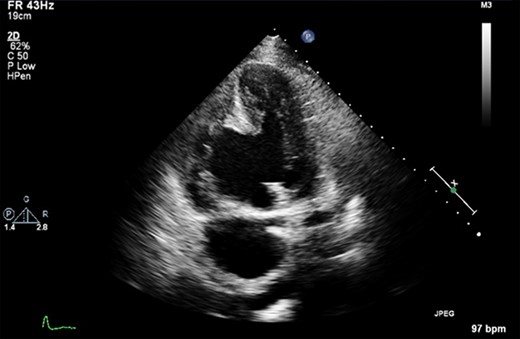

Pre-operative transthoracic echocardiogram (TTE) demonstrated both the left and right ventricles were dilated. Left ventricular (LV) function was mildly reduced, whereas right ventricular (RV) function was severely impaired. A large aneurysm was noted alongside a post-infarction VSD with left to right shunting (Fig. 1). Moderate MR was reported.

A pre-operative still from a TTE demonstrating a large VSD and a large RV aneurysm.